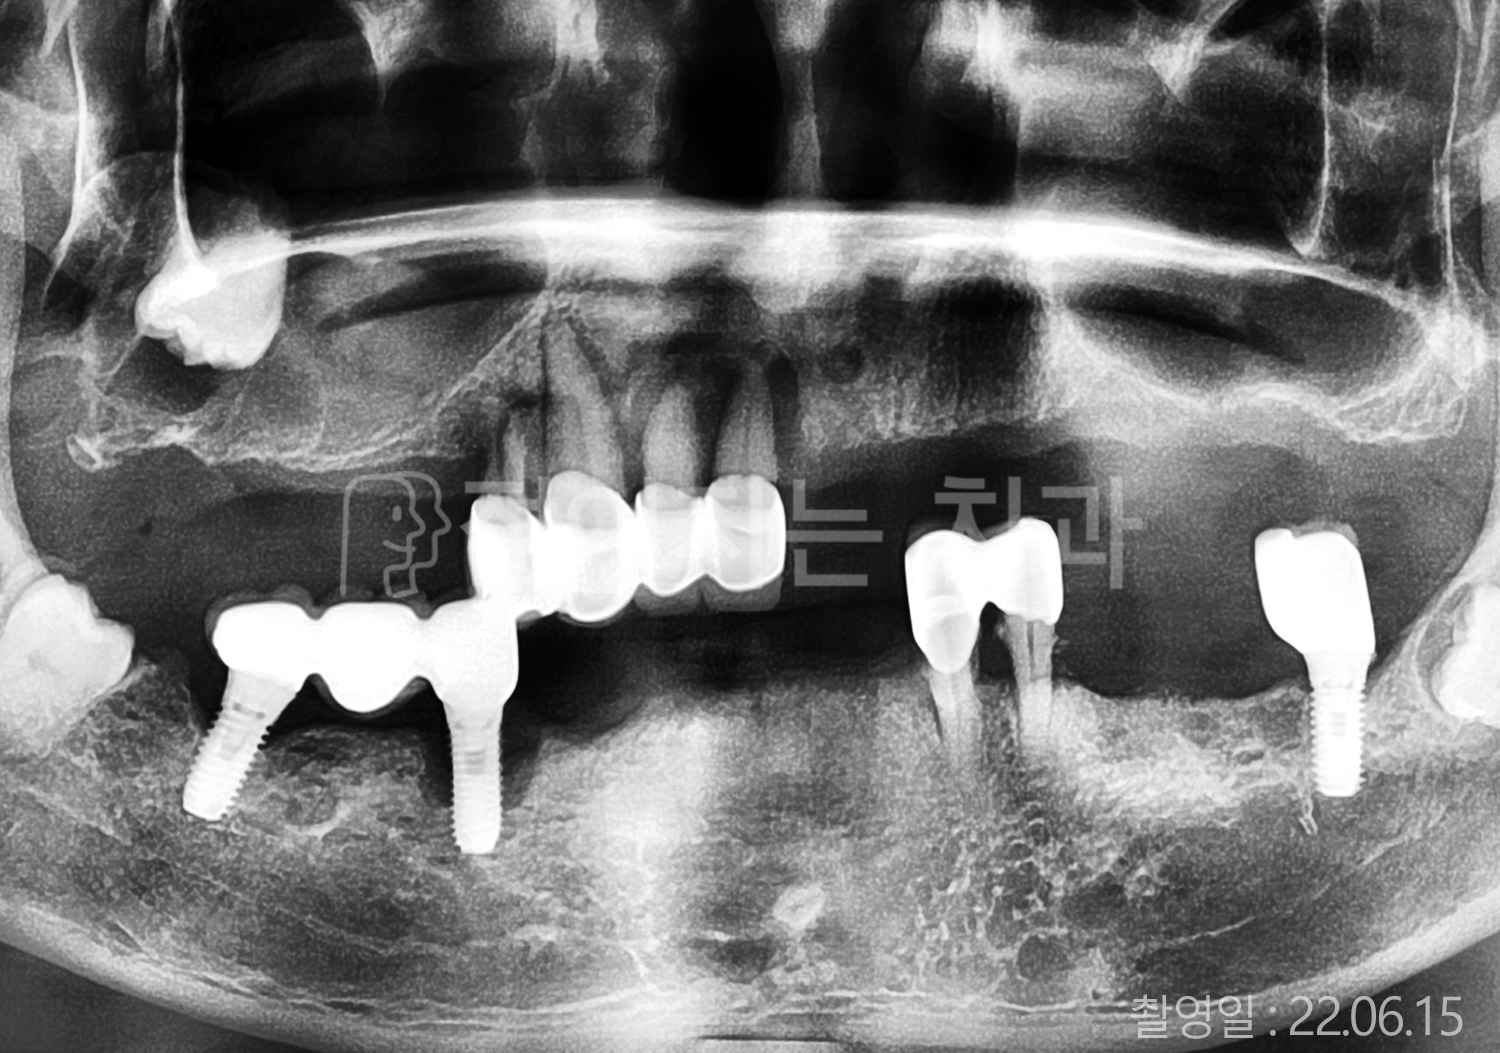

• 50대 고혈압, 당뇨, 고지혈증 전체치아 10개 이상 임플란트

• 50대 고혈압, 당뇨 전체치아 10개 이상 임플란트